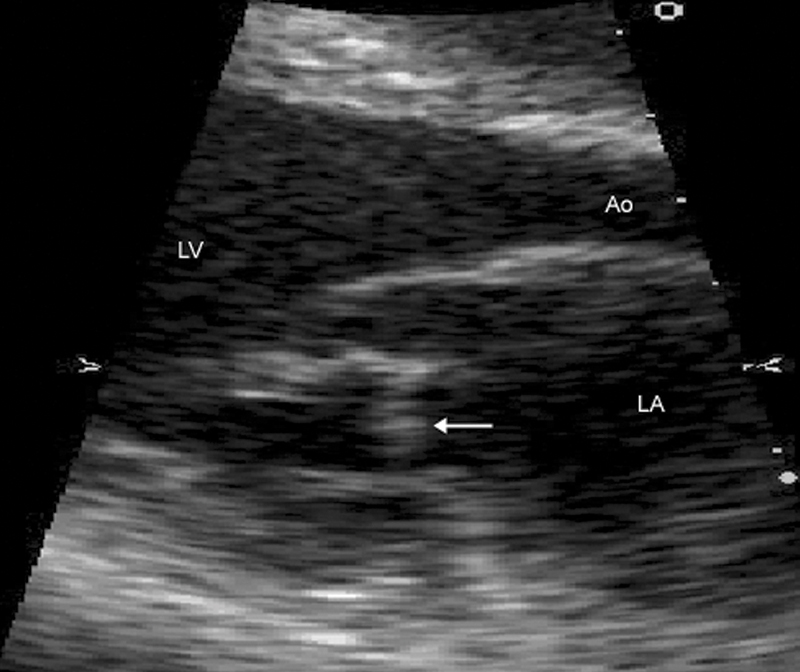

فحوصات تشخيصية لبعض امراض القلب والشرايين التاجية